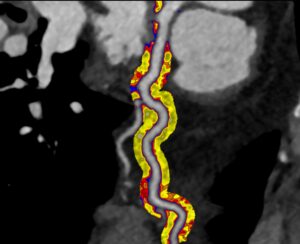

Central Sydney Cardiology is the first centre in Australia to offer CaRi-Heart, an advanced analysis of a standard CT coronary angiogram. CaRi-Heart quantifies an imaging-derived signal associated with coronary inflammation (the Fat Attenuation Index, or FAI) and integrates this with CT findings and clinical risk factors to provide an individualised estimate of future cardiac risk.

A CT coronary angiogram shows the coronary arteries and can identify plaque and narrowing. CaRi-Heart adds an additional layer by analysing changes in the tissue surrounding the coronary arteries that are associated with inflammatory activity. This is not something that can be reliably assessed by the human eye in routine reporting.

FAI stands for Fat Attenuation Index. In simple terms, it is a way of measuring subtle shifts in the characteristics of fat around the coronary arteries on CT. These shifts can occur when the artery wall is biologically “active” or inflamed.

Why is this clinically useful? Coronary risk is not determined only by whether a plaque causes a tight narrowing. Many heart attacks arise from plaques that were not severely obstructive beforehand. Inflammation-related biological activity is one of the drivers of plaque progression and instability. In some people, this signal can be elevated even when plaque is mild, when calcium score is low, or when stenosis is not severe. CaRi-Heart aims to identify this hidden risk signal so prevention can be better tailored.